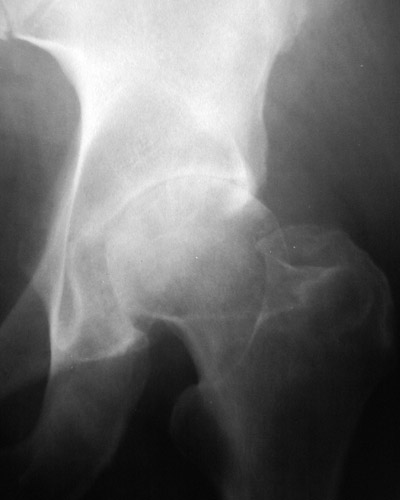

![]() | The plain film of the pelvis above demonstrates joint space narrowing of the left hip in a patient with osteoarthritis. Hip joints are commonly involved, because they are heavy weight-bearing joints. Compare to the hip joint on the right. A close view of this process is shown below. |